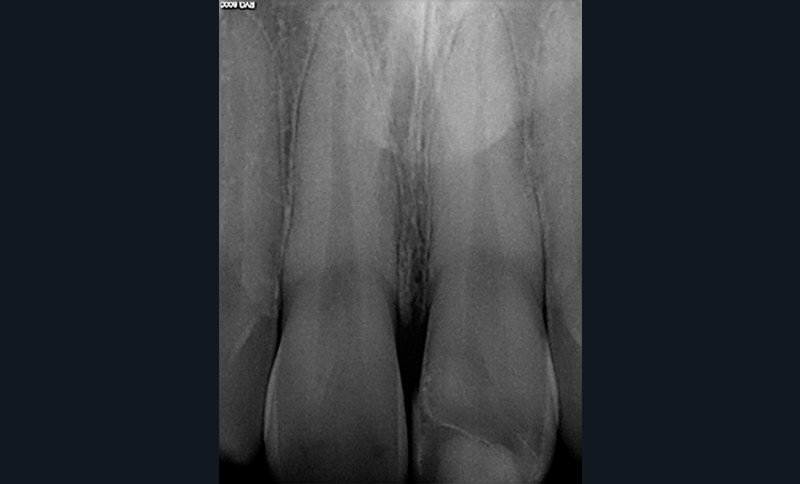

2. Situation après dépose du composite et mise en place du champ opératoire. On observe de nombreuses fêlures amélaires sur la 11 et sur la dent à restaurer.